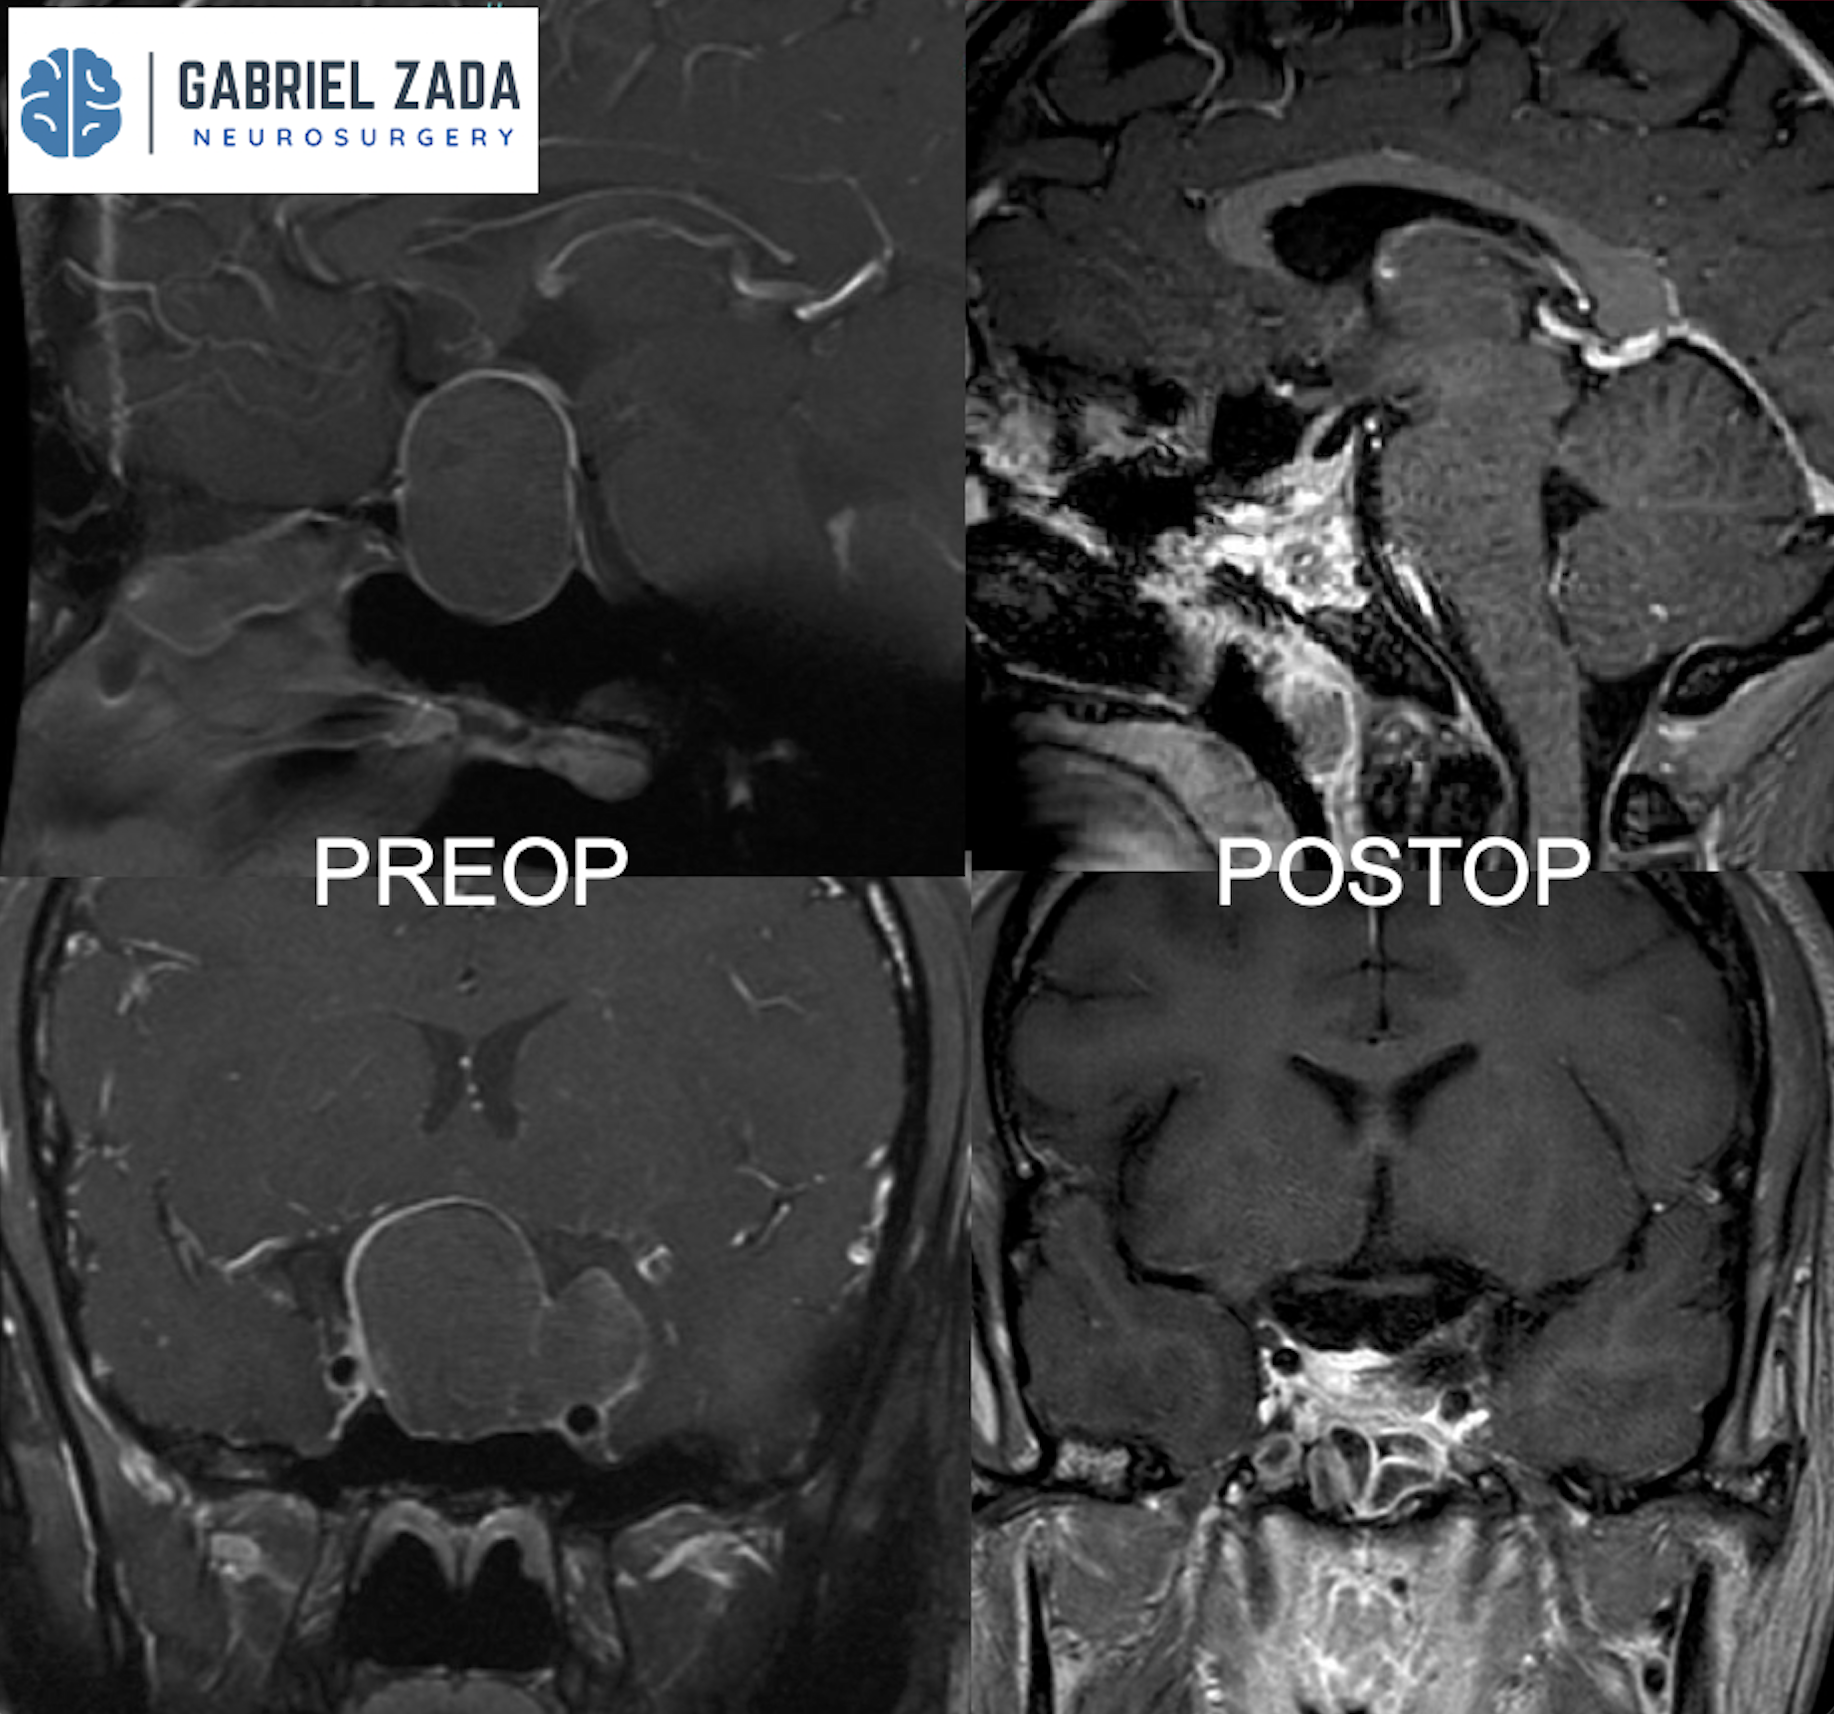

Explore this comprehensive gallery featuring pre‑ and post‑operative imaging of patients with skull‑base tumors treated by Gabriel Zada, MD, MS, FAANS, FACS. These cases highlight Dr. Zada’s expertise in advanced neurosurgical techniques and outcomes.

*Representative cases shown for educational purposes. All images de-identified. Individual results vary.